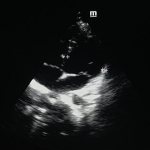

Visual instrumental examinations are carried out using transabdominal ultrasound (ultrasound of the abdominal cavity), CT, radiography, magnetic resonance cholangiopancreatography.

Obviously, in the diagnosis of subcostal pain, imaging methods are of great importance: various types of radiography, ultrasound, and tomography. In some cases, the primary role is given to laboratory analyzes of biological fluids, in others, only a biopsy, endoscopy or diagnostic laparoscopy can provide decisive answers.